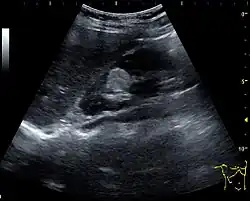

Complex cysts can have membranes dividing the fluid-filled center with internal echoes, calcifications or irregular thickened walls. The complex cyst can be further evaluated with Doppler US, and for Bosniak classification and follow-up of complex cysts, either contrast-enhanced ultrasound (CEUS) or contrast CT is used (Figure 6). The Bosniak classification is divided into four groups going from I, corresponding to a simple cyst, to IV, corresponding to a cyst with solid parts and an 85–100% risk of malignancy.[1] In polycystic kidney disease, multiple cysts of varying size in close contact with each other are seen filling virtually the entire renal region. In advanced stages of this disease, the kidneys are enlarged with a lack of corticomedullary differentiation (Figure 7).[1]

Figure 7. Advanced polycystic kidney disease with multiple cysts.[1]